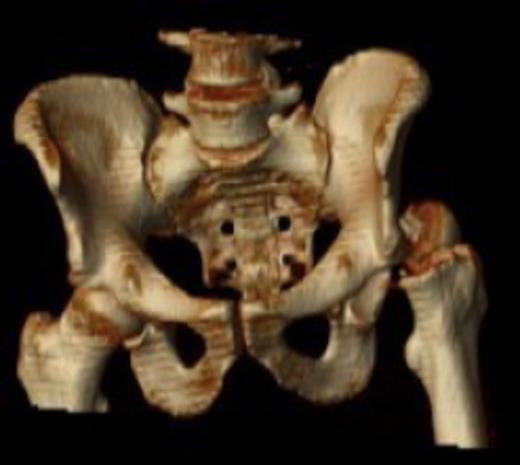

Postoperative care included early-supervised non-weight bearing mobilization for three months. Radiographs at three months showed no early displacement or evidence of avascular necrosis (Fig. 4). The patient progressed to protected full-weight bearing for a further three months.

At one year the patient was walking with a stick and mild limp, he had ninety degrees of hip flexion with limited internal and external rotation. Plain radiographs at this stage confirmed the fracture to be united with no evidence of avascular necrosis. The patient remained on yearly review and continued to function well. He returned to hobbies such as fishing and shooting and was pain free at three and a half years. The most recent review at four and a half years confirmed the presence of avascular necrosis (Fig. 5) however from a symptomatic point of view he is still able to maintain an active lifestyle with little pain.